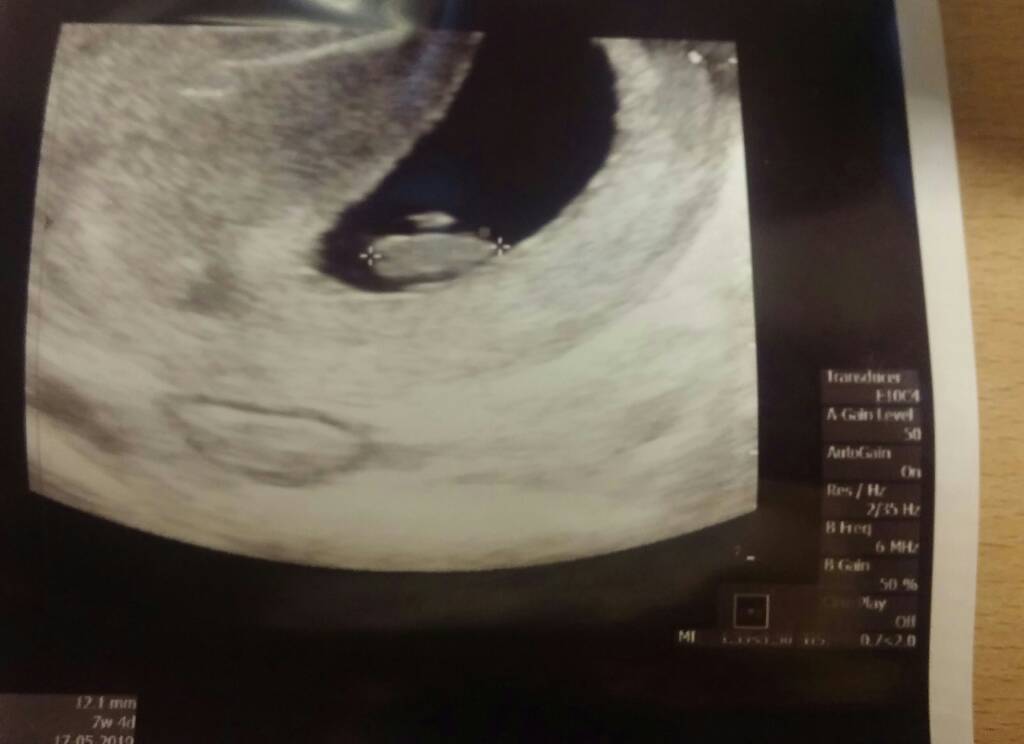

Moje zdjęcie z USG, ja tak dla odmiany, 3 razy doktora pytałam czy na pewno nie ma tam nigdzie drugiego bąbla schowanego, bo powiedział że owulacja była podwójna.... a bliźniaki w domu już mam i teraz wystarczy mi jedno na prawdę ;)

• IMG_2038.JPG

IMG_2038.JPG

1,4 MB · Wyświetleń: 210